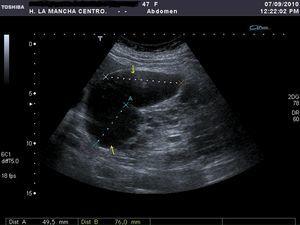

Se solicitó la realización de una ecografía urgente en la que se detectó que hígado y ambos riñones presentaban múltiples formaciones quísticas, pero no se describieron lesiones indicativas de quistes complicados (figura 1). En principio se interpretó el cuadro como una agudización de su insuficiencia renal crónica secundaria a una situación funcional, y se contempló la posibilidad de que existiera una infección quística. Se pautó sueroterapia y un antibiótico (ciprofloxacino), aunque el resultado del urocultivo recibido a los 4 días fue negativo. En las primeras 48 horas desde el ingreso mejoró progresivamente su función renal, pero tras una semana de ingreso la paciente sufre un deterioro brusco de su estado general, anemización con caída del hematocrito de 12 puntos y de la hemoglobina de 4 g/dl (Hb 7,4 g/dl, Hto 21%), caída tensional (TA 93/58 mmHg) y taquicardia (91 sístoles). En un segundo análisis de orina se objetivó una microhematuria solicitándose una segunda ecografía abdominal, hallándose  hematoma intraquístico en la región anterior y en el polo superior del riñón derecho (figura 2). Se completó el estudio mediante una tomografía computarizada abdomino-pélvica sin contraste intravenoso, que confirmó la existencia de una hemorragia intraquística y descartando la presencia de un sangrado retroperitoneal (figura 3 A y figura 3 B).

Figura 1. Ecografía renal derecha al ingreso.